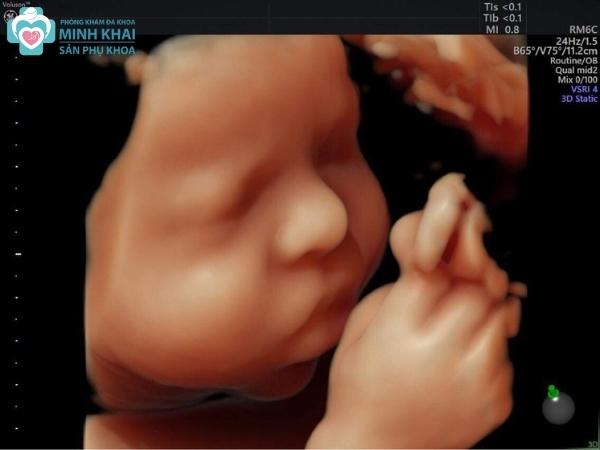

Tháng thứ mấy nên siêu âm 5D để có được hình ảnh siêu âm sắc nét nhất? Trong thực tế việc siêu âm thai 5D ngay từ tuần 13 - 14 thai kỳ đã cho ra những bức ảnh màu của thai nhi sống động và tổng quát về cấu tạo của bé.

Phụ huynh có thể theo dõi toàn bộ hành động cũng như ngắm nhìn được cơ thể, đường nét khuôn mặt, biểu cảm của bé yêu thông qua màn hình. Hơn thế nữa, siêu âm thai 5D còn giúp quan sát và đánh giá được cả tim mạch, hệ xương, hệ thần kinh. Nó có thể siêu âm được cả những vị trí khó để tái tạo lại hình ảnh qua các mặt cắt một cách rõ ràng mà công nghệ 2D, 3D chưa có khả năng làm được.